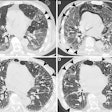

Round atelectasis on PET FDG imaging: The images below demonstrate the typical CT and FDG PET findings in round atelectasis. On CT, there are thickened lung markings and vessels which swirl into the lesion that abuts an area of pleural thickening. Note the lack of metabolic activity in round atelectasis on PET imaging. |